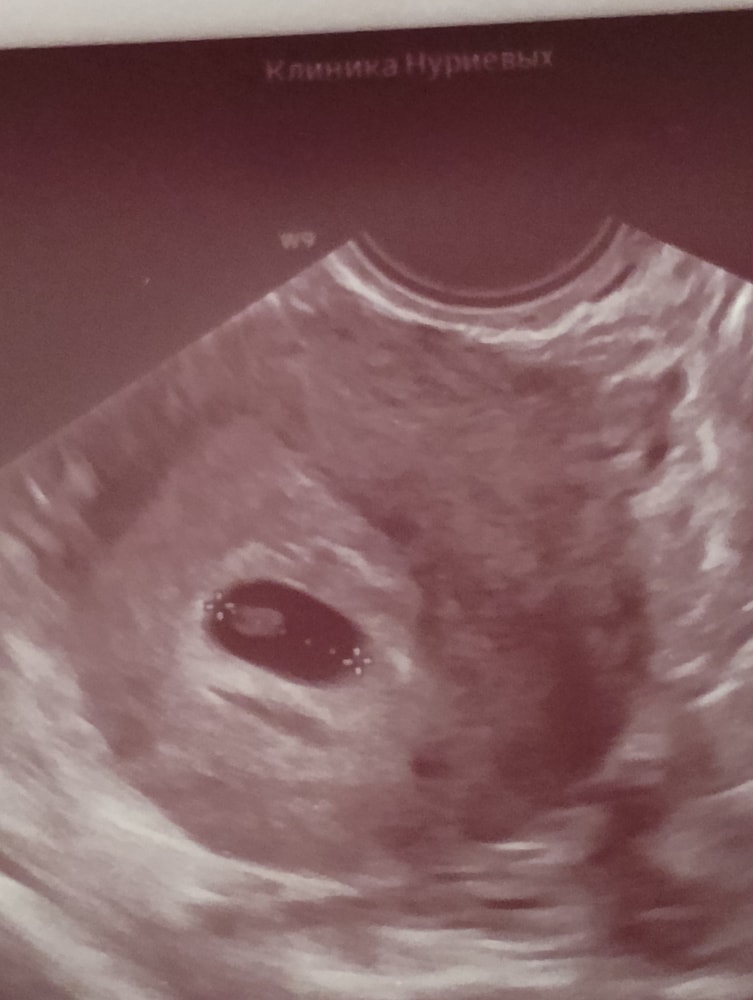

Первое фото🎀

гематом,отслоек нет

Девочки, не сильно большой ХГч ???

Думаю, не разделился ли эмбрион?